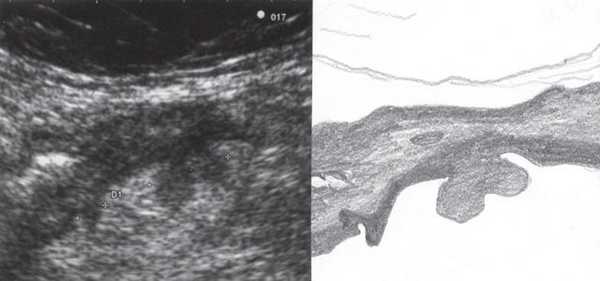

При УЗИ были выявлены диффузные изменения печени и поджелудочной железы, признаки хронического бескаменного холецистита, ангиомиолипома левой почки (без динамики за несколько лет), состояние после экстирпации матки с придатками. В левой подвздошной области соответственно зоне максимальной пальпаторной болезненности на протяжении 9 см отмечалось утолщение стенок толстой кишки до 6-7 мм (рис. 1). Перистальтика кишки отсутствовала, гаустрация была слабо выражена, при этом визуализировалось несколько болезненных при надавливании датчиком выпячиваний пониженной эхогенности, размером от 7 до 20 мм (рис. 2, а, б) с тонкой стенкой до 0,9-1,1 мм и наличием в некоторых из них фрагментов кишечного содержимого и газа (рис. 3, а, б).

Рис. 1. Эхографическая картина дивертикулита. Трансабдоминальное исследование линейным датчиком 7,5 МГц.

"Симптом пораженного полого органа".

Рис. 2. Эхографическая картина дивертикулита. Трансабдоминальное исследование линейным датчиком 7,5 МГц.

а) Продольный срез.

б) Поперечный срез.